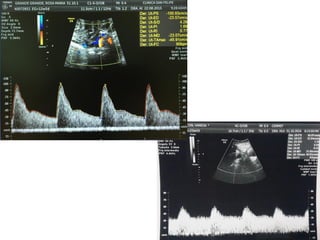

VALORACIÓN DV

• Semanas 11+0-13+6 y la LCC entre 45-84 mm. El feto no

debe moverse.

• El tamaño de la imagen debe ser tal que el tórax y abdomen

fetal ocupen toda la pantalla. Se debe obtener un corte

sagital medio del tronco fetal.

• Se debe usar el Doppler color para demostrar la vena

umbilical, el ductus venoso y el corazón fetal. La ventana

del Doppler pulsado debe ser pequeña (0,5-1,0 mm) y debe

situarse en la zona de aliasing normalmente en amarillo

• El ángulo de insonación debe ser menor de 30 grados.

• El filtro debe ser de baja frecuencia (50-70 Hz), para

permitir la visualización de la onda completa.

• La velocidad de barrido debe ser alta (2-3 cm/s), para

obtener una forma más ancha y poder evaluar mejor la onda

A.